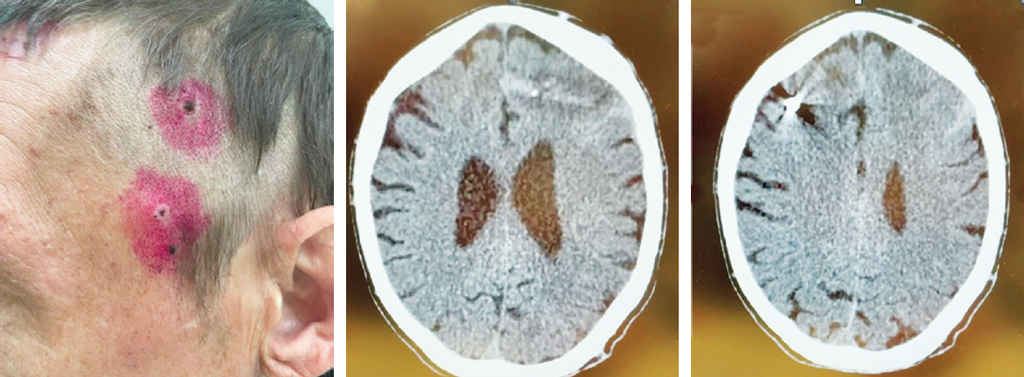

Fig. 6. Patient G. No active complaints consistent with brain injury, conscious, no neurological symptoms. Upon examination, the entrance holes of a penetrating blind craniocerebral wound are visualized in the left temporal region (at the time of injury, consciousness was not lost). CT of the head — a hypodense wound channel with the presence of foreign bodies of bone density was detected in the left frontal region, the wound channel goes upwards into the right frontal region of the brain with the presence of a foreign body of metallic density

Рис. 6. Пациент Г. Без активных жалоб, соответствующих травме мозга, в ясном сознании, без неврологической симптоматики. При осмотре в левой височной области визуализируются входные отверстия проникающего слепого черепно-мозгового ранения (в момент получения травмы сознание не терял). КТ головы — в левой лобной области выявлен гиподенсный раневой канал с наличием инородных тел костной плотности, раневой канал идет вверх в правую лобную область мозга с наличием инородного тела металлической плотности